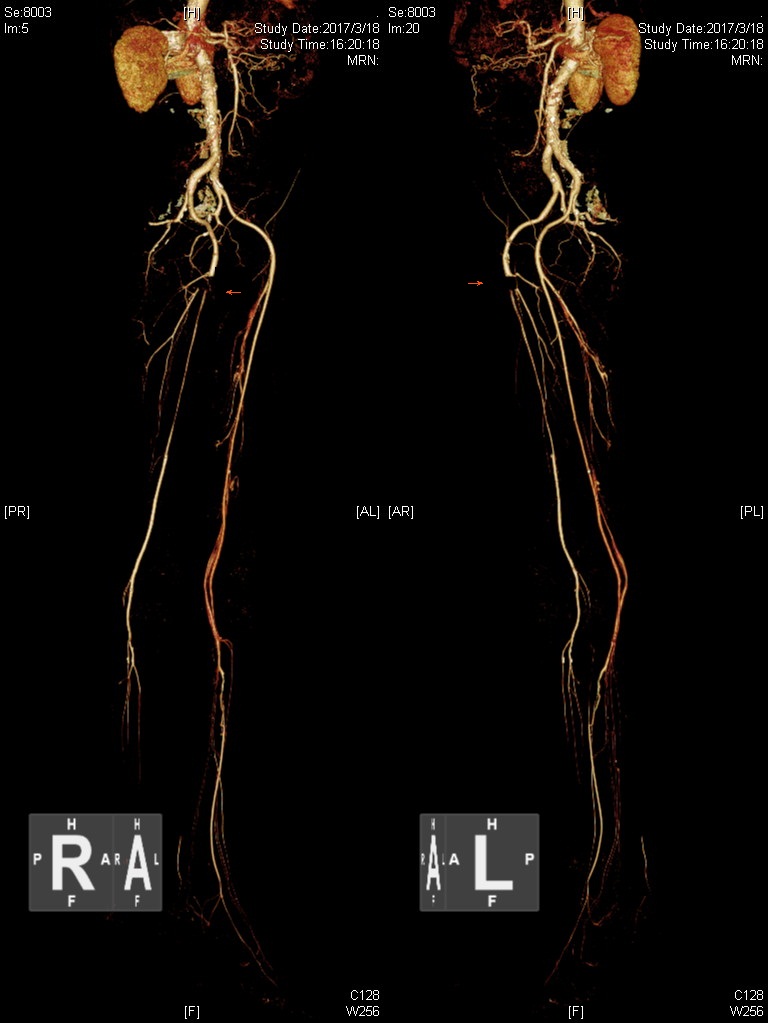

患者李伯伯1天前突发右下肢发凉、麻木,颜色紫绀,下肢动脉超声及CT造影检查明确为右侧股动脉血栓形成。股动脉是向下肢供血的主干动脉,急性缺血可导致下肢坏死。北京清华长庚医院血管外科团队使用AngioJet技术顺利抽吸动脉血栓,恢复血流供应。

术前CTA检查可见右侧股动脉血栓形成,血流中断。

血栓抽吸完成后,动脉恢复通畅血流。